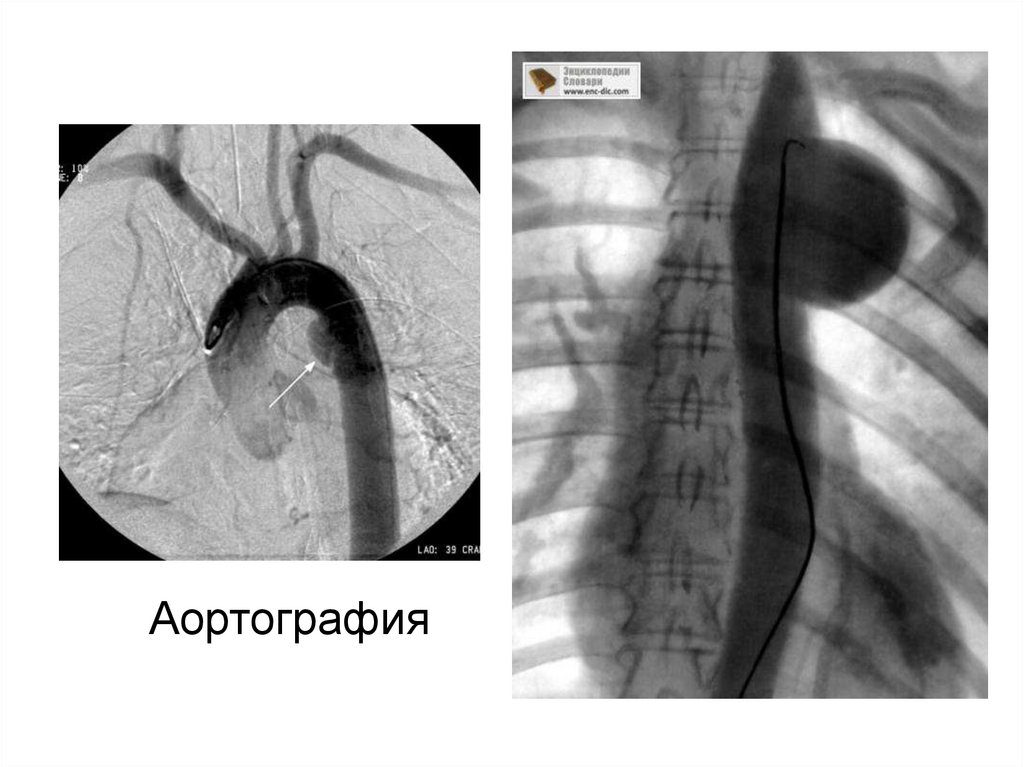

30. Аортография

31.